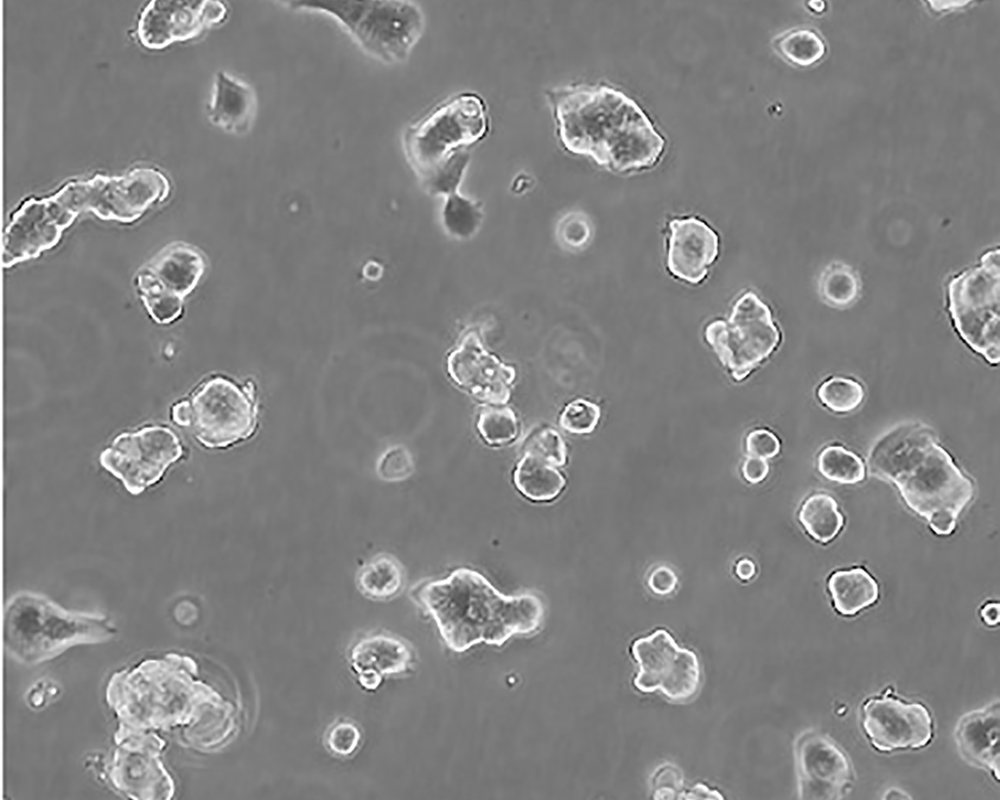

ZR-75-1 [ZR751]

中文名稱 人乳腺癌細(xì)胞

組織來源 浸潤(rùn)性導(dǎo)管癌;腹水轉(zhuǎn)移;女性

生長(zhǎng)特性 adherent

形態(tài)特征 epithelial

細(xì)胞描述 該細(xì)胞產(chǎn)生高水平的黏液素MUC-1 mRNA,低水平的MUC-2 mRNA,但不表達(dá)MUC-3基因;表達(dá)雌激素受體。